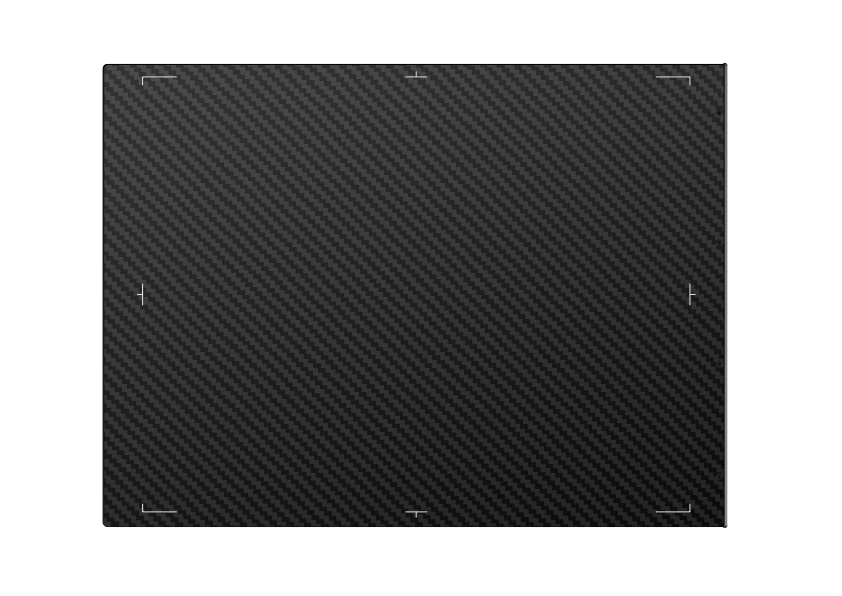

Iray Mars 1013X High-Performance Medical Equipment X Ray Machine Cassette-size Wireless a-Si Flat Panel Detector for horse

Model: PSKU0118

| Product Name | Iray Mars 1013X High-Performance Medical Equipment X Ray Machine Cassette-size Wireless a-Si Flat Panel Detector for horse |

| SKU | PSKU0118 |

1. Features:

1) Best-in-class 100 μm pixel pitch with 16-bit ADC for more image details

2) Direct deposition Csl, with excellent DQE at all frequencies

3) Full AED control, exposure at any time

4) Large capacity battery design, with 8+hours battery life

5) Lightweight design with lPx5 ingress protection

6) Supports a fast workflow for a better user experience

7) Detector Technology: Amorphous Silicon

8) Scintillator: CsI

9) Active Area (inch): 10×13

10) Pixel Matrix: 2528 x 3318

11) Pixel Pitch (um): 100

12) AD Conversion (bit): 16

13) Battery Autonomy (h): 8h